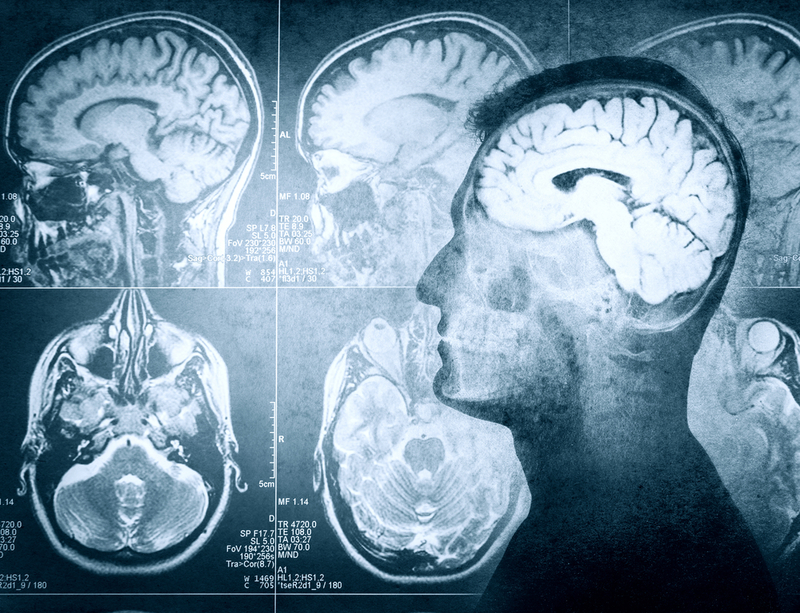

US scientists at the University of California San Francisco (UCSF) have found a new pattern of brain activity that may help develop new therapies in the future to treat mood disorders like depression.

Most human brain research on mood disorders has relied on studies in which participants lie in a functional magnetic resonance imaging (fMRI) scanner and look at upsetting images or listen to sad stories, reports Xinhua news agency. However, the scientists from UCSF Weill Institute for Neurosciences recruited 21 patient volunteers with epilepsy who had had 40 to 70 electrodes implanted on the brain's surface and in deeper structures of the brain to record brain activities for seven to 10 days.